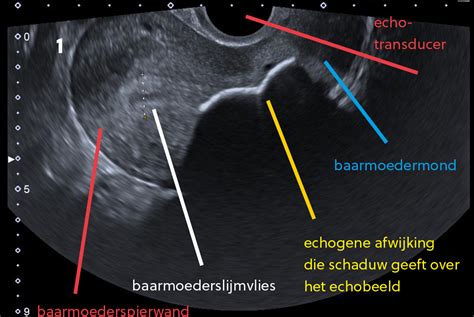

- Een echo van de buik maken om de baarmoeder, placenta en baby te beoordelen.